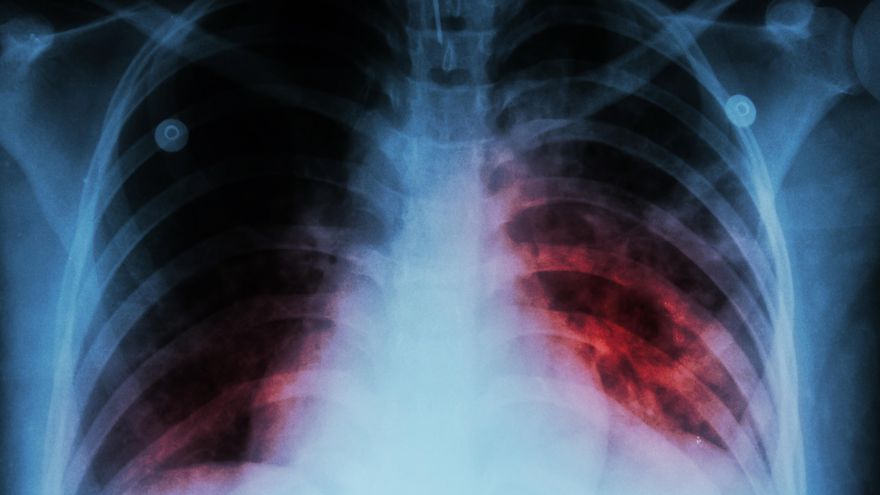

Imagen ilustrativa de un paciente infectado con tuberculosis.

Esta enfermedad es causada por una bacteria llamada Mycobacterium tuberculosis que, por medio del aire, invade el organismo humano. Una vez dentro, viaja a través del sistema respiratorio hasta alojarse en los pulmones y provocar una infección.

Al menos en el 95% de los casos, la bacteria solo se aloja en el organismo sin desarrollar síntomas aparentes, provocando una infección latente. En el resto de los casos, se presenta una infección activa en la cual estos gérmenes se multiplican y rompen las barreras de contención, desencadenando una infección pulmonar con consecuencias potencialmente devastadoras.